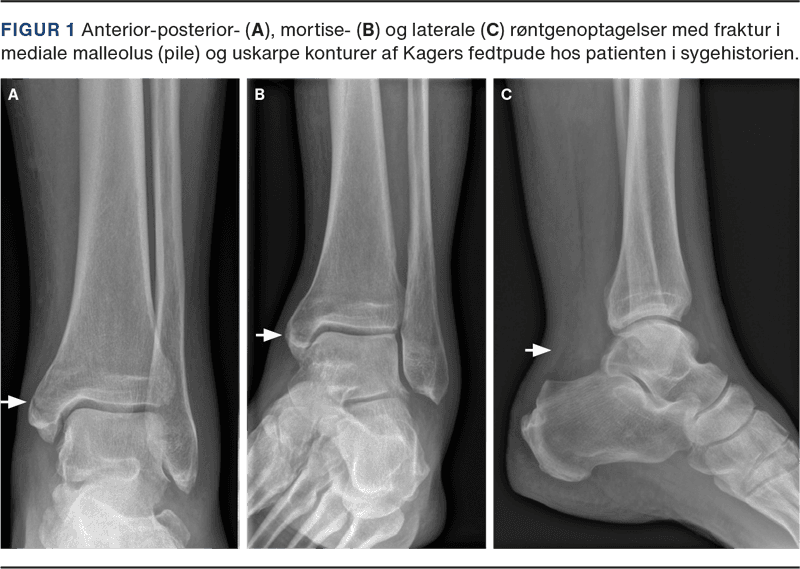

En 59-årig mand mødte i skadestuen med funktionsnedsættelse og smerter i venstre fod. Da han skiftede dæk på bilen, skred hans venstre fod fra hjulnøglen og ramte underlaget. Subjektivt beskrev han et pludseligt smæld i venstre læg. Objektivt observeredes der hævelse, misfarvning og smerter i bagkanten af mediale malleolus, en palpabel defekt i akillessenen samt positiv Matles test og positiv Thompsons test. Anterior-posterior-, mortise- og laterale røntgenoptagelser afslørede en udisloceret, oblik MMF samt sløring og uskarpe konturer af Kagers fedtpude (Figur 1).